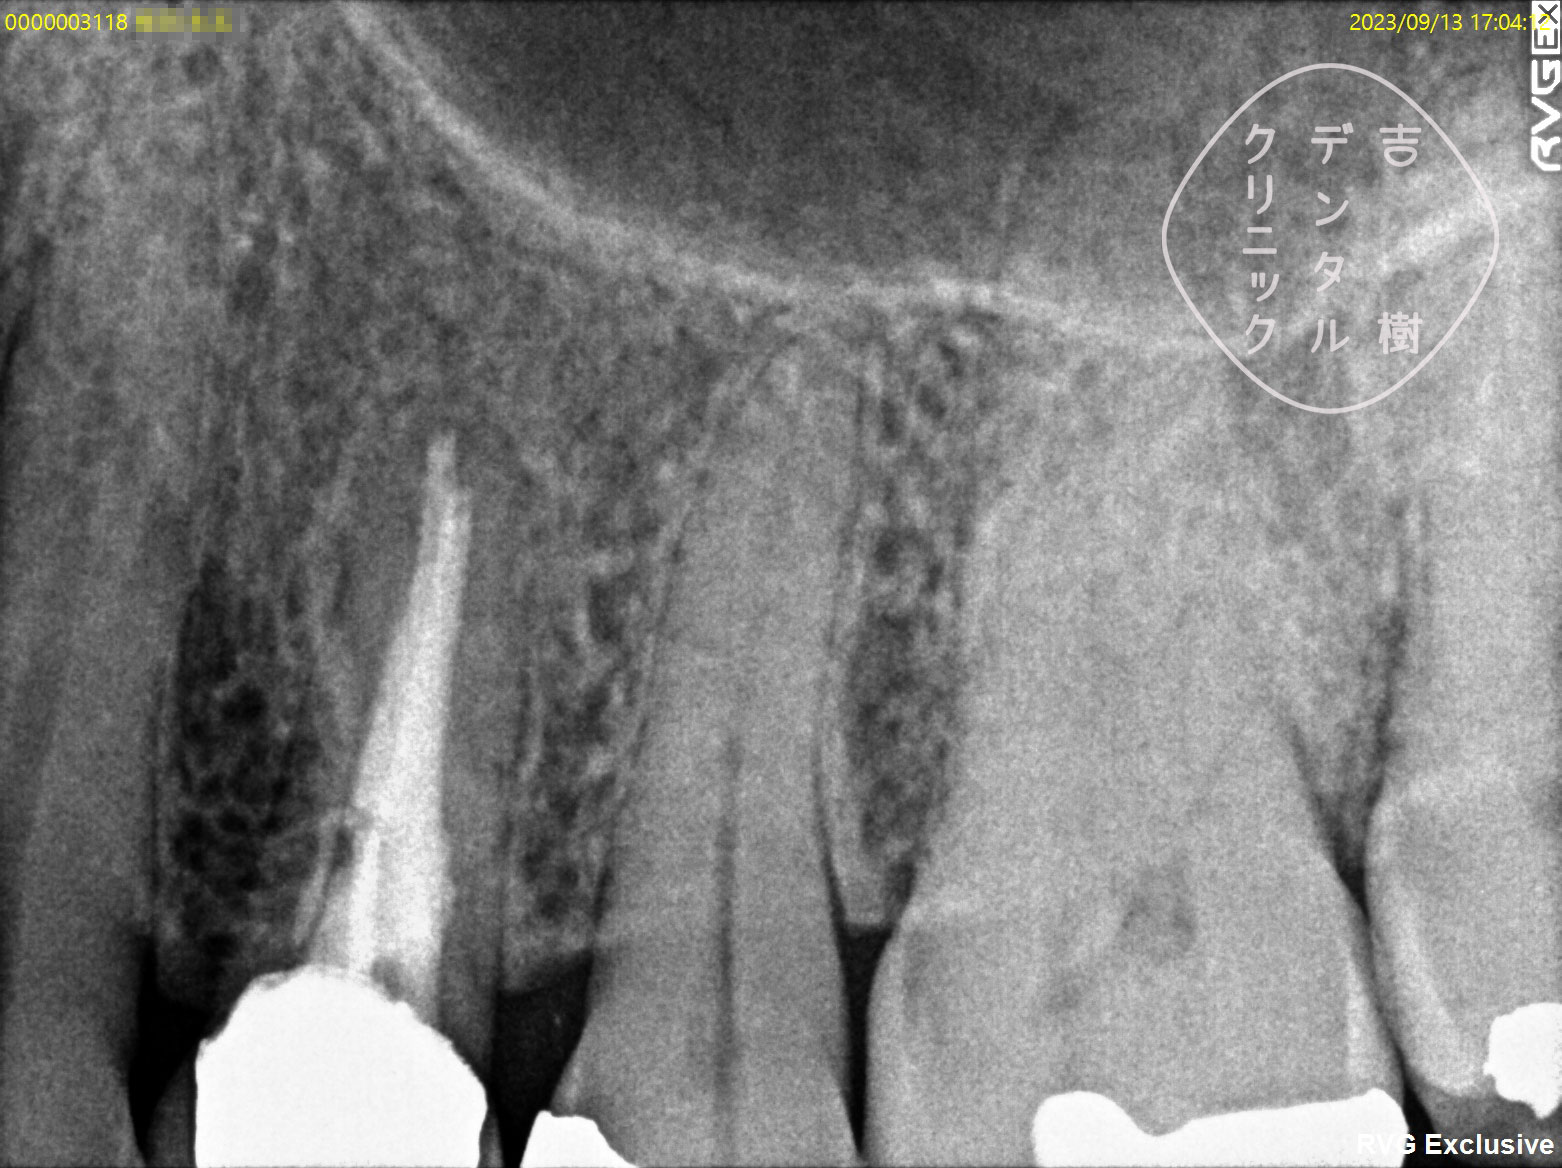

他院で抜歯と診断されたが、当院で根管治療を行い抜歯せずに治療できたケース。

根管治療を行う際には、まず、画像診断を行うことで歯の形状を確認します。通常、多くの歯科医院では「2次元」のレントゲンが使用されますが、この方法では初期の患部を見つけることが難しく、根管の複雑な形状を確実に把握するには不十分です。

そのため、当院では「3次元」の撮影が可能な「CT」を使用しています。CTはお口の周りを360度回転しながら撮影することで、レントゲンでは確認することができなかった細かい部分まで詳細に把握することができます。